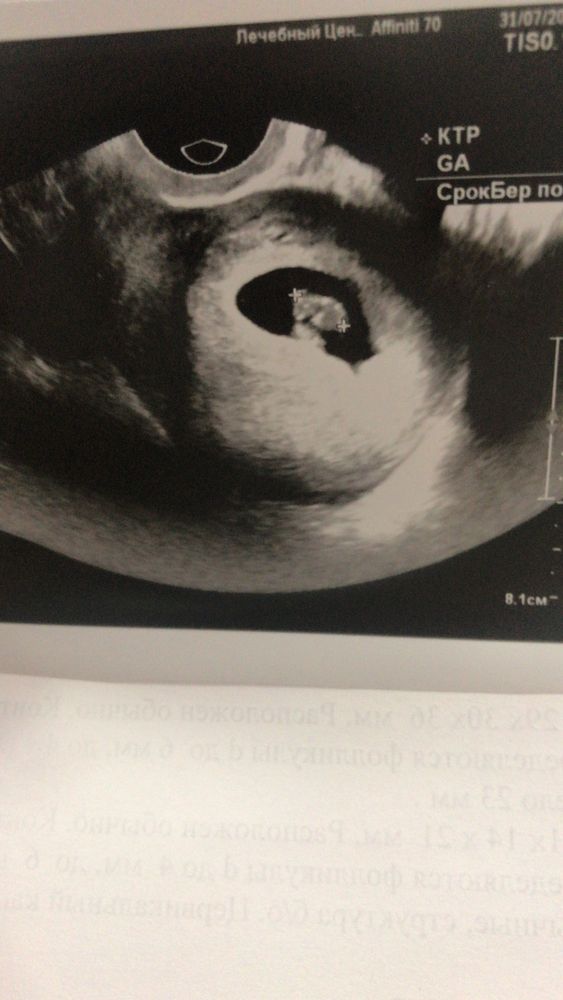

Официально беременна. Срок 7 недель и 1 день

Первое узи, размер плодного яйца ❤ 9 недель ❤